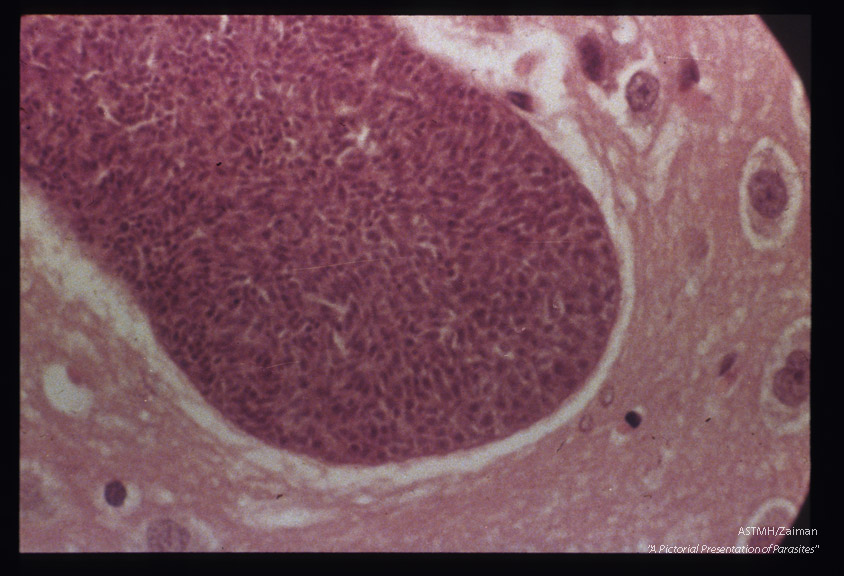

Hematoxylin-eosin stained sections of mouse brain.

M organism of Frenkel

Description: Hematoxylin-eosin stained sections of mouse brain.